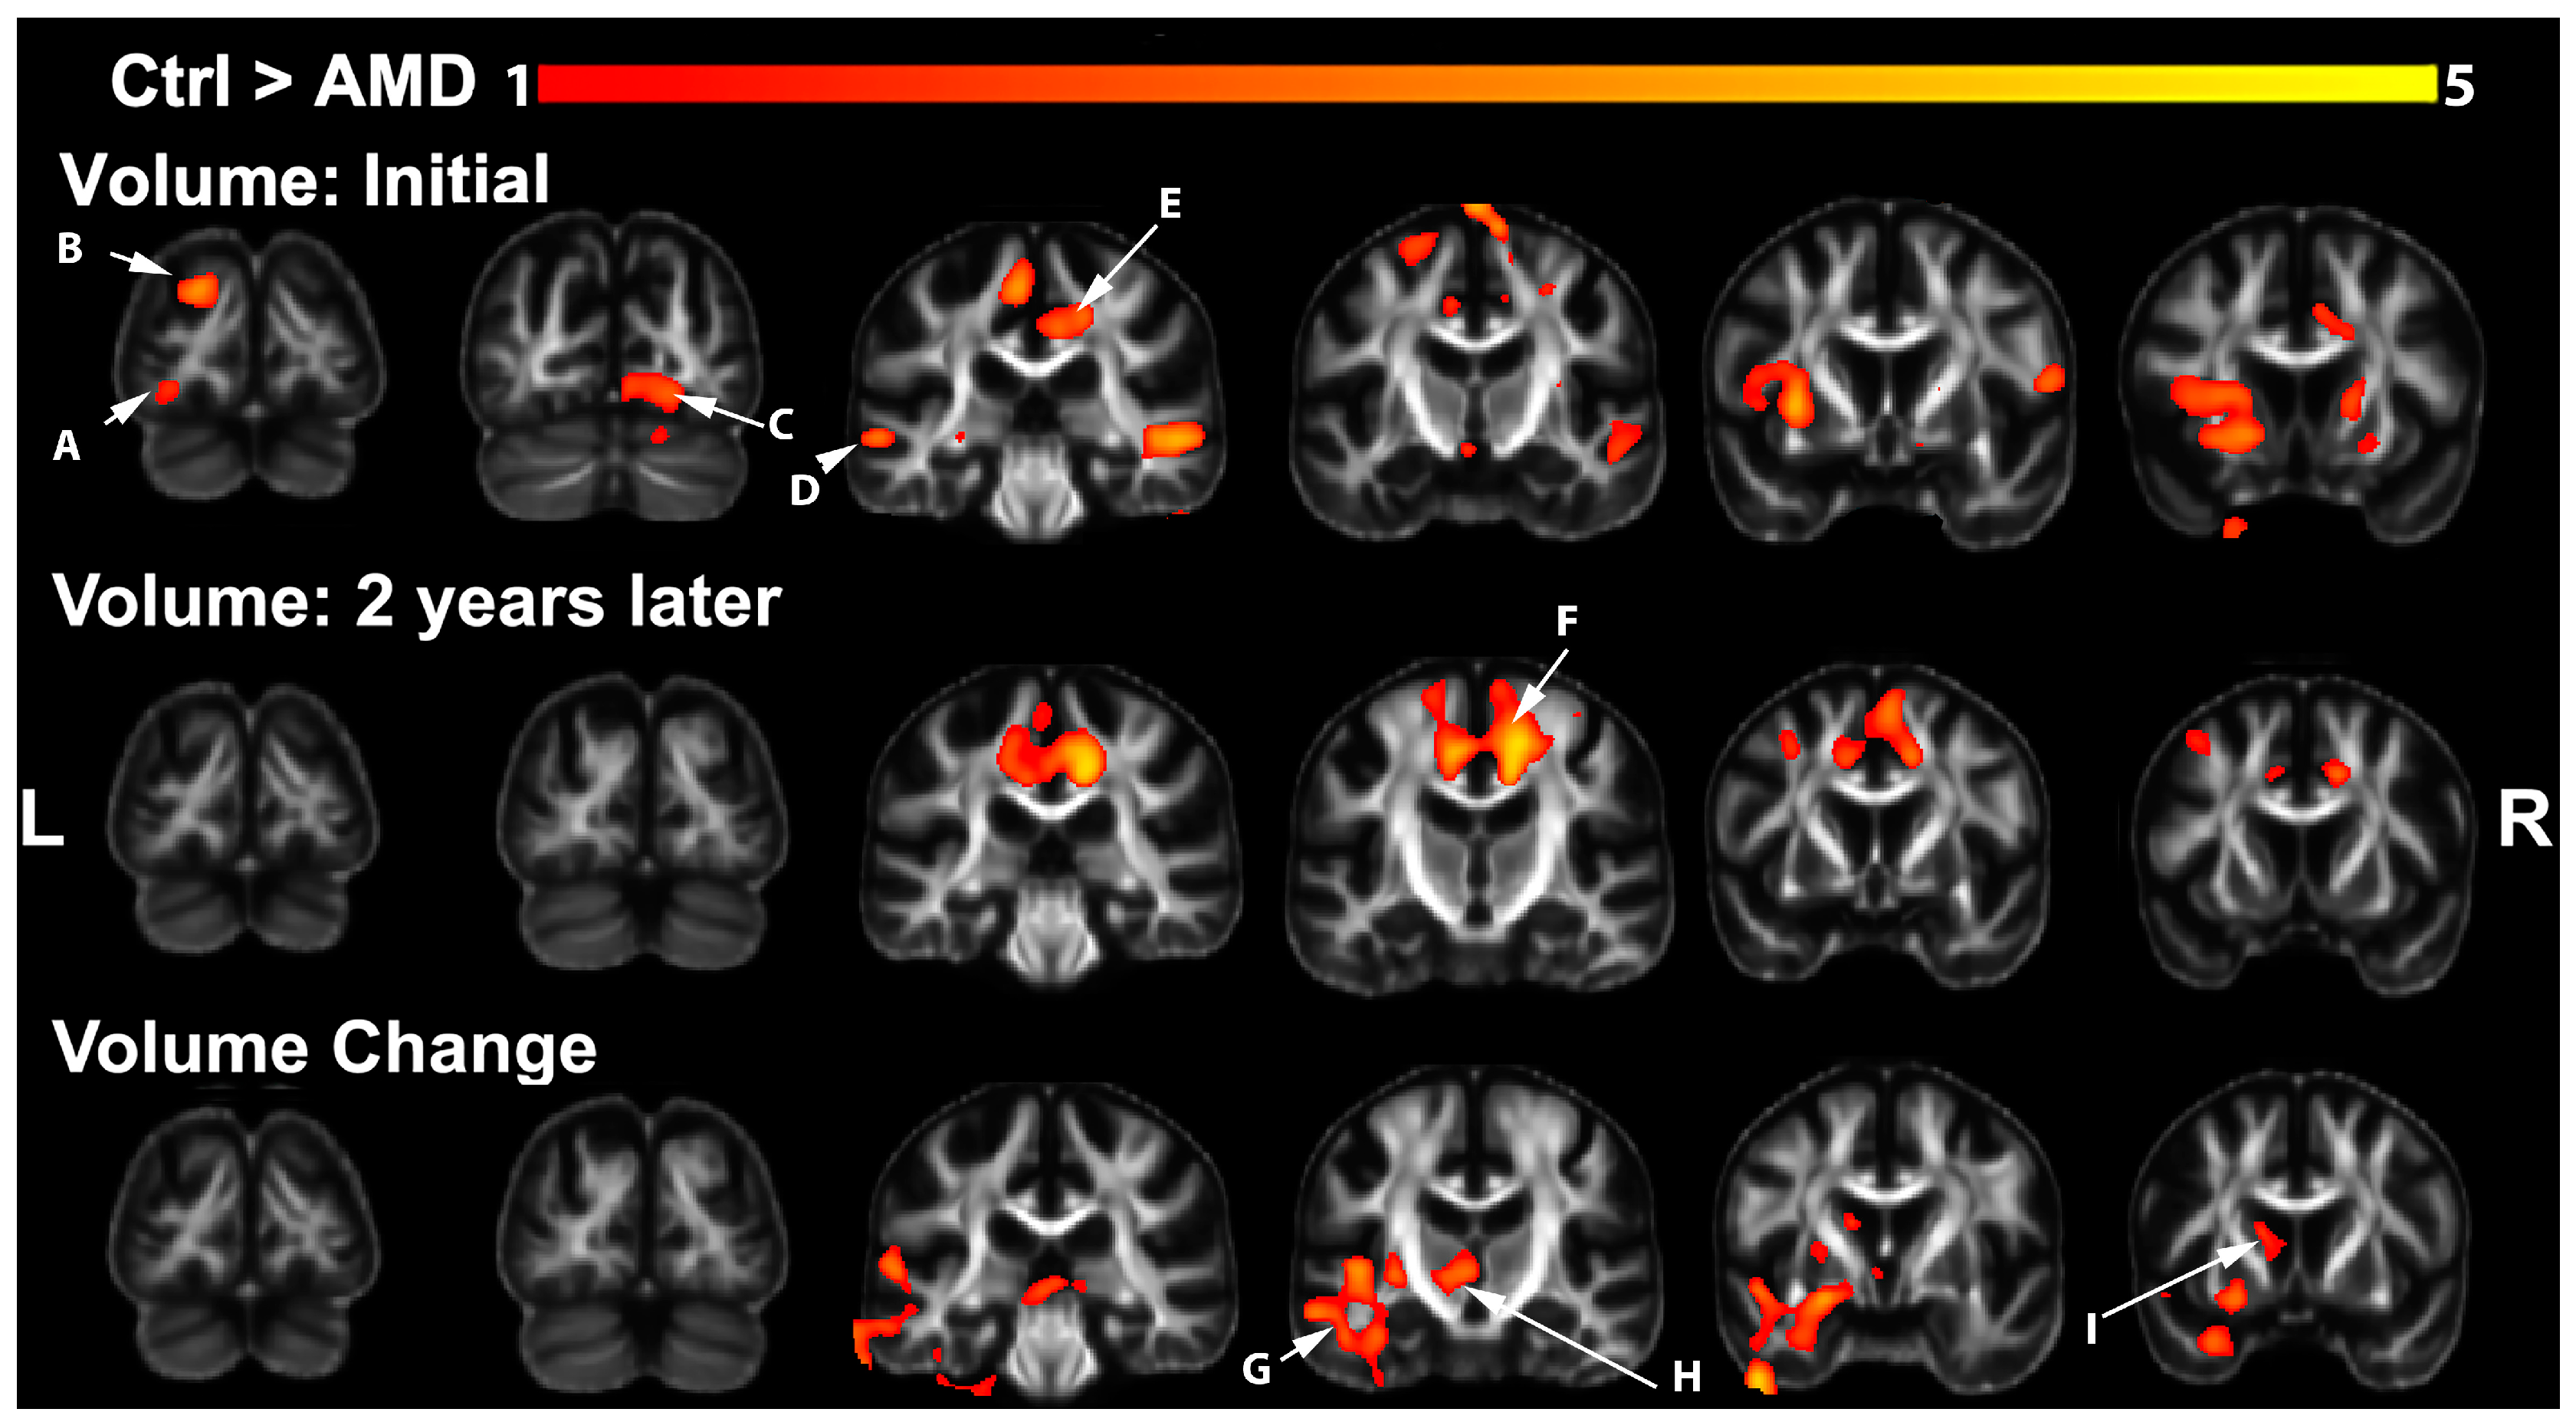

3.1. Volumetric Changes in AMD Participants